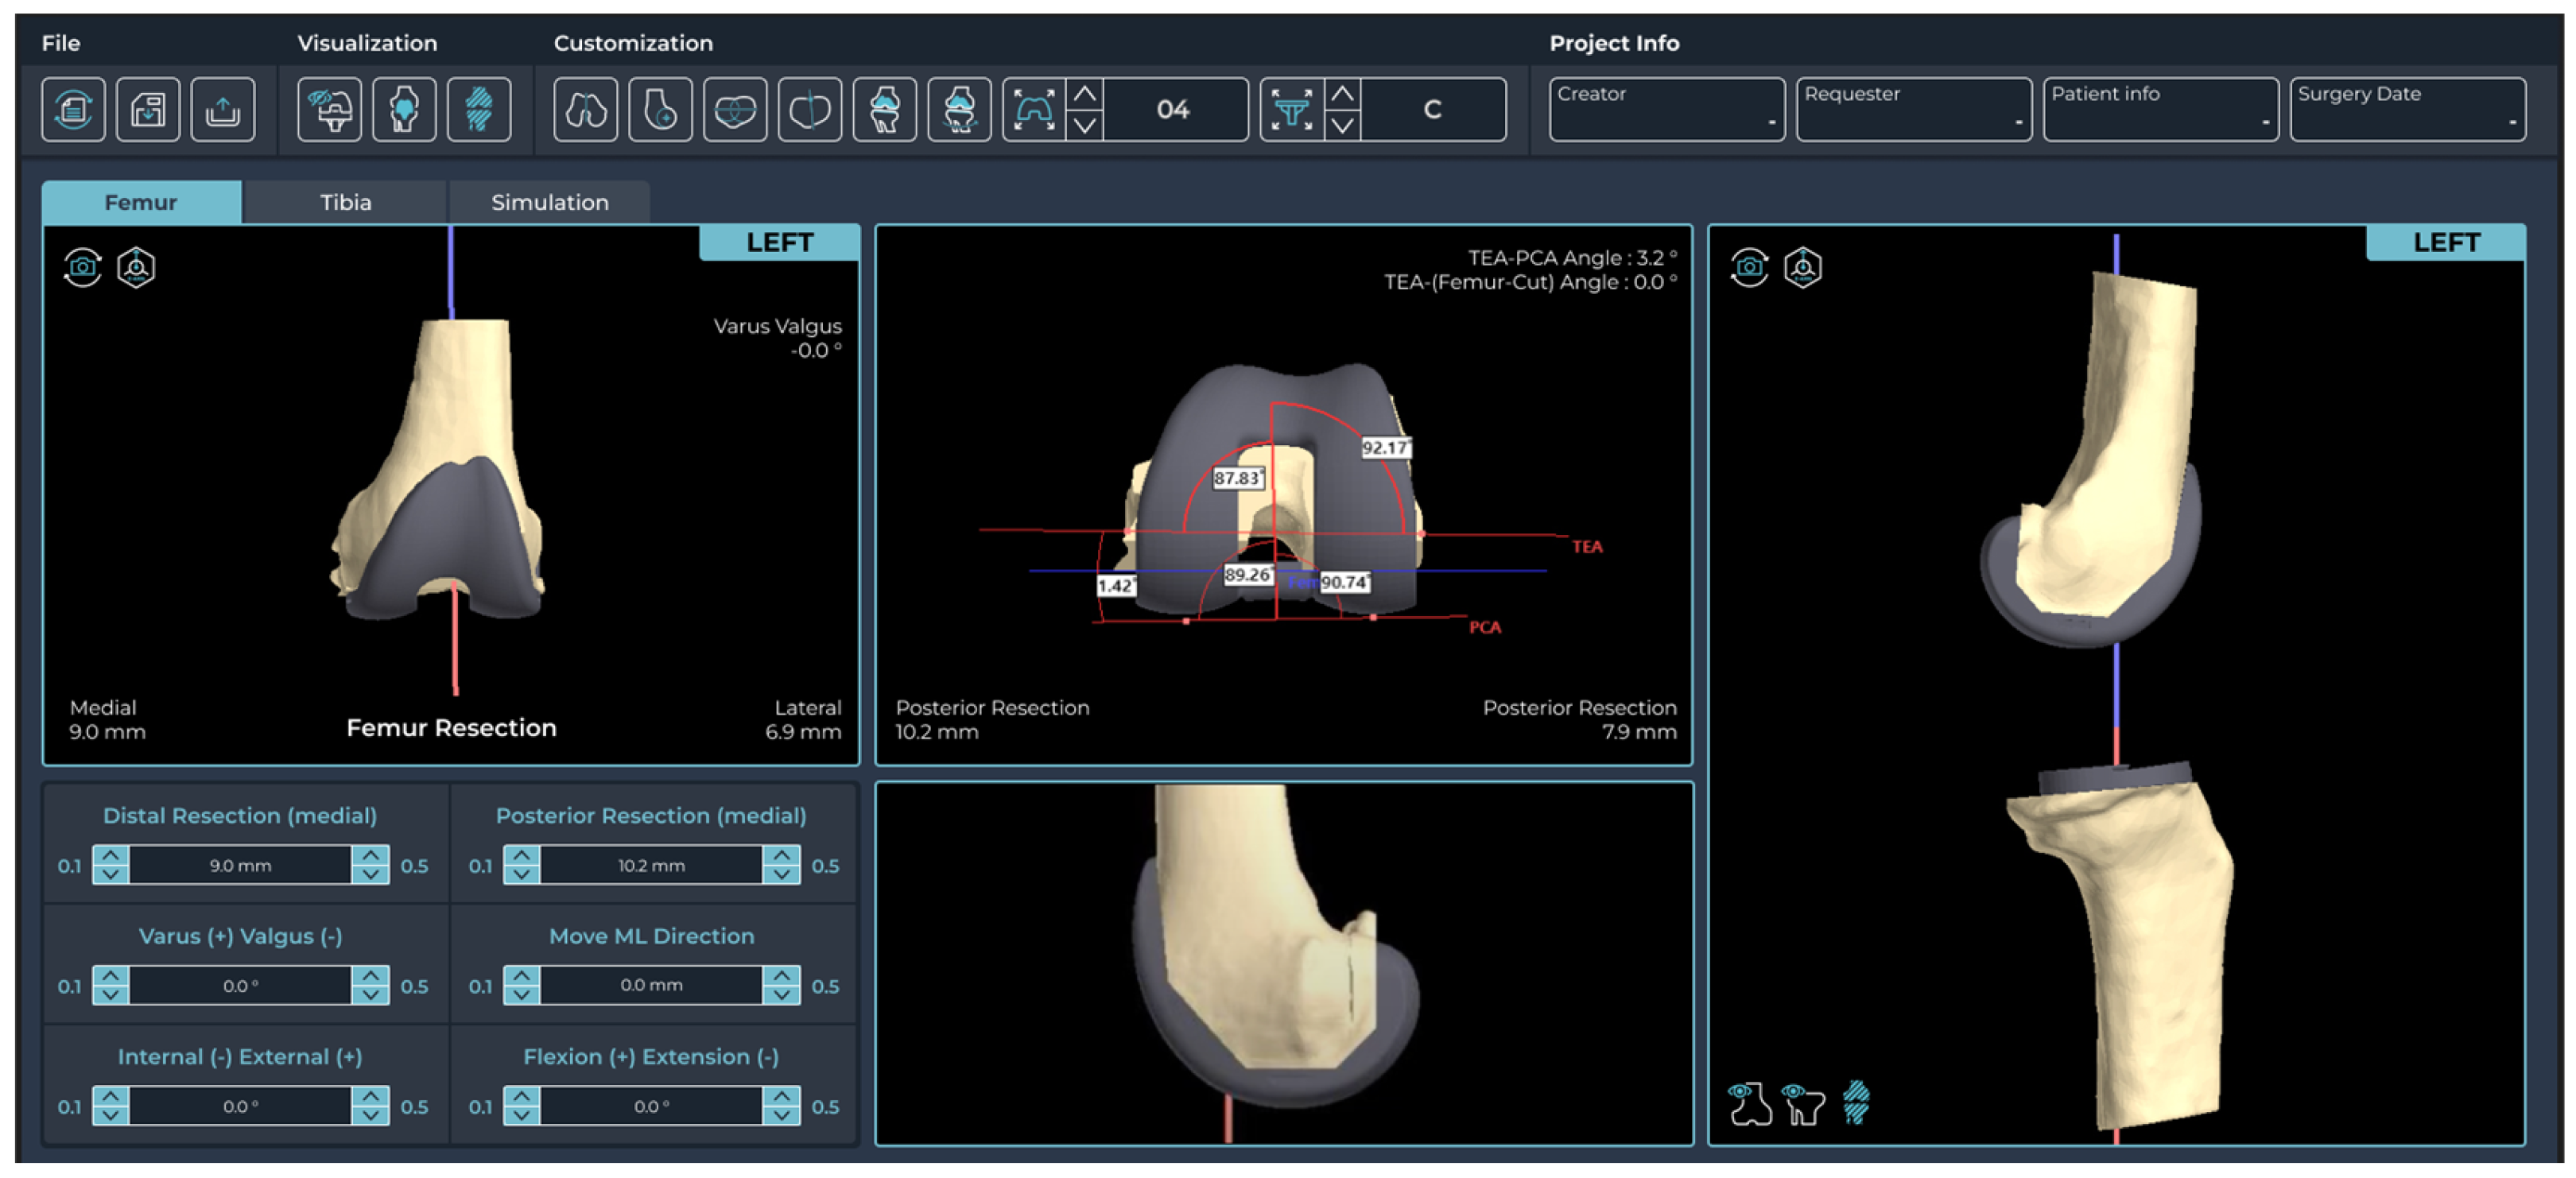

2.2. Pre-Planning and PSI Design Methods

2.3. Outcome Measurements